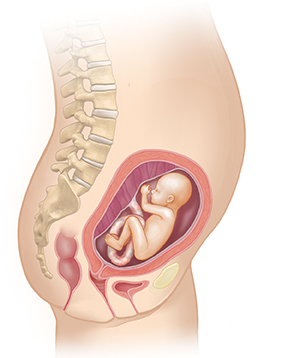

Month 5

You may feel your baby move. After a growth spurt, your baby nears 10 inches.